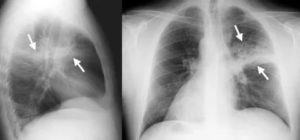

Крупозная пневмония на рентгене характеризуется уплотнением стенки плевры и застоем жидкости в плевральной полости. Для оценки пораженных участков проводится рентгенограмма в прямой и боковой проекциях.

На снимке виден однородно затемненный сегмент, имеющий неровные границы, или доля легкого.

Пневмония переходит в стадию серого опеченения на 4-6-е сутки после начала заболевания. В это время пораженная доля легких плотная с фиброзными налетами на плевре. Признаки пневмонии на рентгеновских снимках: видно изменение легочного контура, отсутствие четкой структуры корня, а также фиброзные тяжки.

На рентгене крупозная форма болезни проявляется следующими признаками:

- Ярко выраженные крупные тени, затрагивающие доли легкого целиком. Могут быть поражены оба легкого.

- Средостение смещается в сторону наиболее воспаленного легкого.

- На куполах диафрагмы отчетливо видны признаки деформации.

- Рисунок легочной ткани может не просматриваться.

Крупозная пневмония легче всего выявляется при рентгенологическом исследовании. Тем не менее для постановки точного диагноза врачи предпочитают делать рентгеновские снимки в двух проекциях. Это дает им возможность определить число пораженных воспалением сегментов органа и определить состояние средостения.